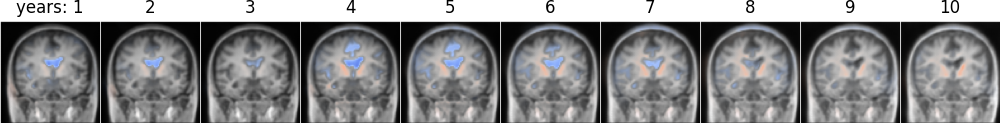

In addition, we demonstrate our model’s ability to interpolate between images and extrapolate beyond the last image in the timeseries. We generate images by sampling a standard multivariate normal in the latent space, and pass it through the decoder with the original image and scalar variables. The random latent sample is fixed across all panels, and only the elapsed time is changed. In Fig. 4, we predict the trajectory annually over 10 years for one individual in the test set with disease status 4 (LMCI) and only two real images available (extrapolation beyond the 4th year). We visualize structural changes over time by calculating a smooth optical flow estimate, and overlaying the divergence of the flow field. Values close to 0 are transparent, positive (expansion) is shown in blue, and negative (contraction) is shown in red. We observe expansion in the ventricular space over time including its inferior horn in the temporal lobe, and contraction of nearby brain structures, in accordance with the AD aging process.